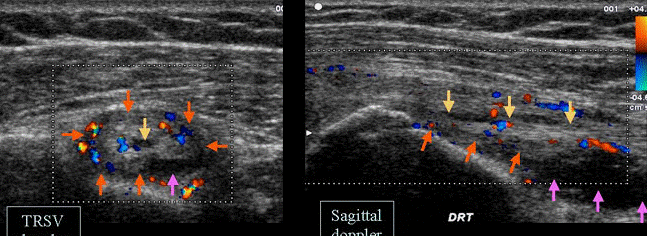

TENOSINOVITA BICEPSULUI

FISURA BICEPSULUI(sageata galbena

INGROSAREA TENDONULUI – SAGEATA PORTOCALIE

EPANSAMENT PERITENDINOS-sag.mov

Hipervascularizatie intrea si peritendinoasa